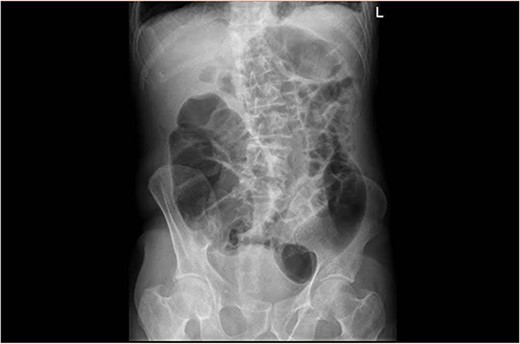

A 89-year-old male patient was admitted to the emergency department complaining of generalized abdominal pain for 4 days. The pain was associated with repeated vomiting and obstipation. He also reported a history of chronic constipation. However, he denied any history of melena, hematochezia, weight loss, night sweats or fever. His past medical history revealed a history of prostatic cancer and pulmonary fibrosis caused by tuberculosis. The patient was diagnosed with symptomatic gallstones two years prior to his presentation, after undergoing an enhanced CT scan of the abdomen (Fig. 1) for abdominal pain. Although he was offered cholecystectomy, he refused the surgery due to his high-risk medical condition.

Enhanced CT scan of the abdomen confirming the presence of a 2.5-cm gallstone.

Upon clinical examination, the patient was vitally stable. Abdominal examination revealed a distended abdomen with generalized tenderness. Digital rectal examination revealed an empty rectum with no palpable masses. Laboratory investigations were unremarkable (Table 1). Abdominal X-ray was done (Fig. 2) and showed dilated large bowel loops suggestive of bowel obstruction. Enhanced CT scan of the abdomen and pelvis was obtained (Figs 3–5) and showed a dilated large bowel loop, with air fluid level. A 2.5-cm gallstone was noted, impacting the sigmoid colon and causing partial large bowel obstruction. There was evidence of pneumobilia with air foci within the gallbladder with a suspected fistula with the hepatic flexure.